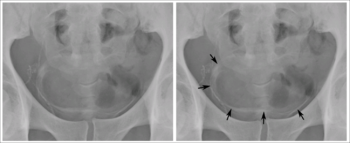

Tình trạng calci hóa hay dày cứng thành bàng quang trên phim chụp x quang thẳng vùng chậu, trên một ca nam giới 44 tuổi vùng Sahara. Điều này do sán máng ở hệ niệu. Nhiễm trùng liên tục có thể gây ra phản ứng u hạt và xơ hóa trong các cơ quan bị nhiễm phải, và khi đó biểu hiện triệu chứng bao gồm: